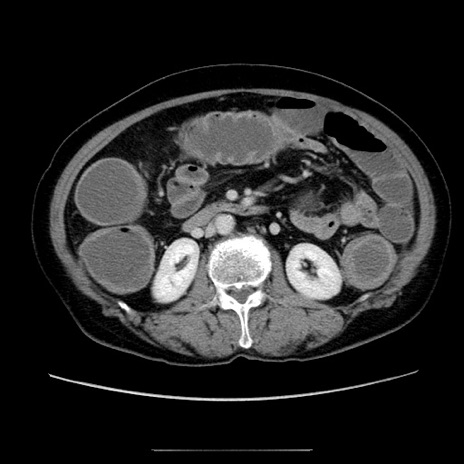

【症例】70歳代女性

【主訴】お腹が張る

【現病歴】1週間くらい前から腹部膨満の自覚あり。昨日夜から増悪したため、本日救急外来受診。

【身体所見】意識清明、BT 36.5℃、BP 165/106mmHg、HR 80bpm、SpO2 98%、腹部:膨満、軟、自発痛・圧痛なし、触診にて不快感あり、腸蠕動音:減弱

【データ】WBC 12600、CRP 1.04